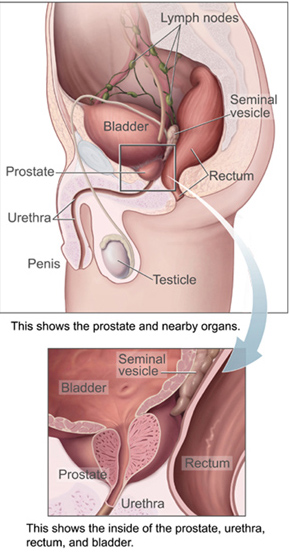

Where It Begins: Prostate Anatomy

The prostate gland is located below the urinary bladder and in front of the rectum. It surrounds part of the urethra, the tube that carries urine out of the body.

Functions of the Prostate:

Anatomy of the male pelvic region highlighting the prostate gland

Functions of the Prostate:

- Produces fluid that contributes to semen

- Supports normal urinary and reproductive function

Anatomy of the male pelvic region highlighting the prostate gland